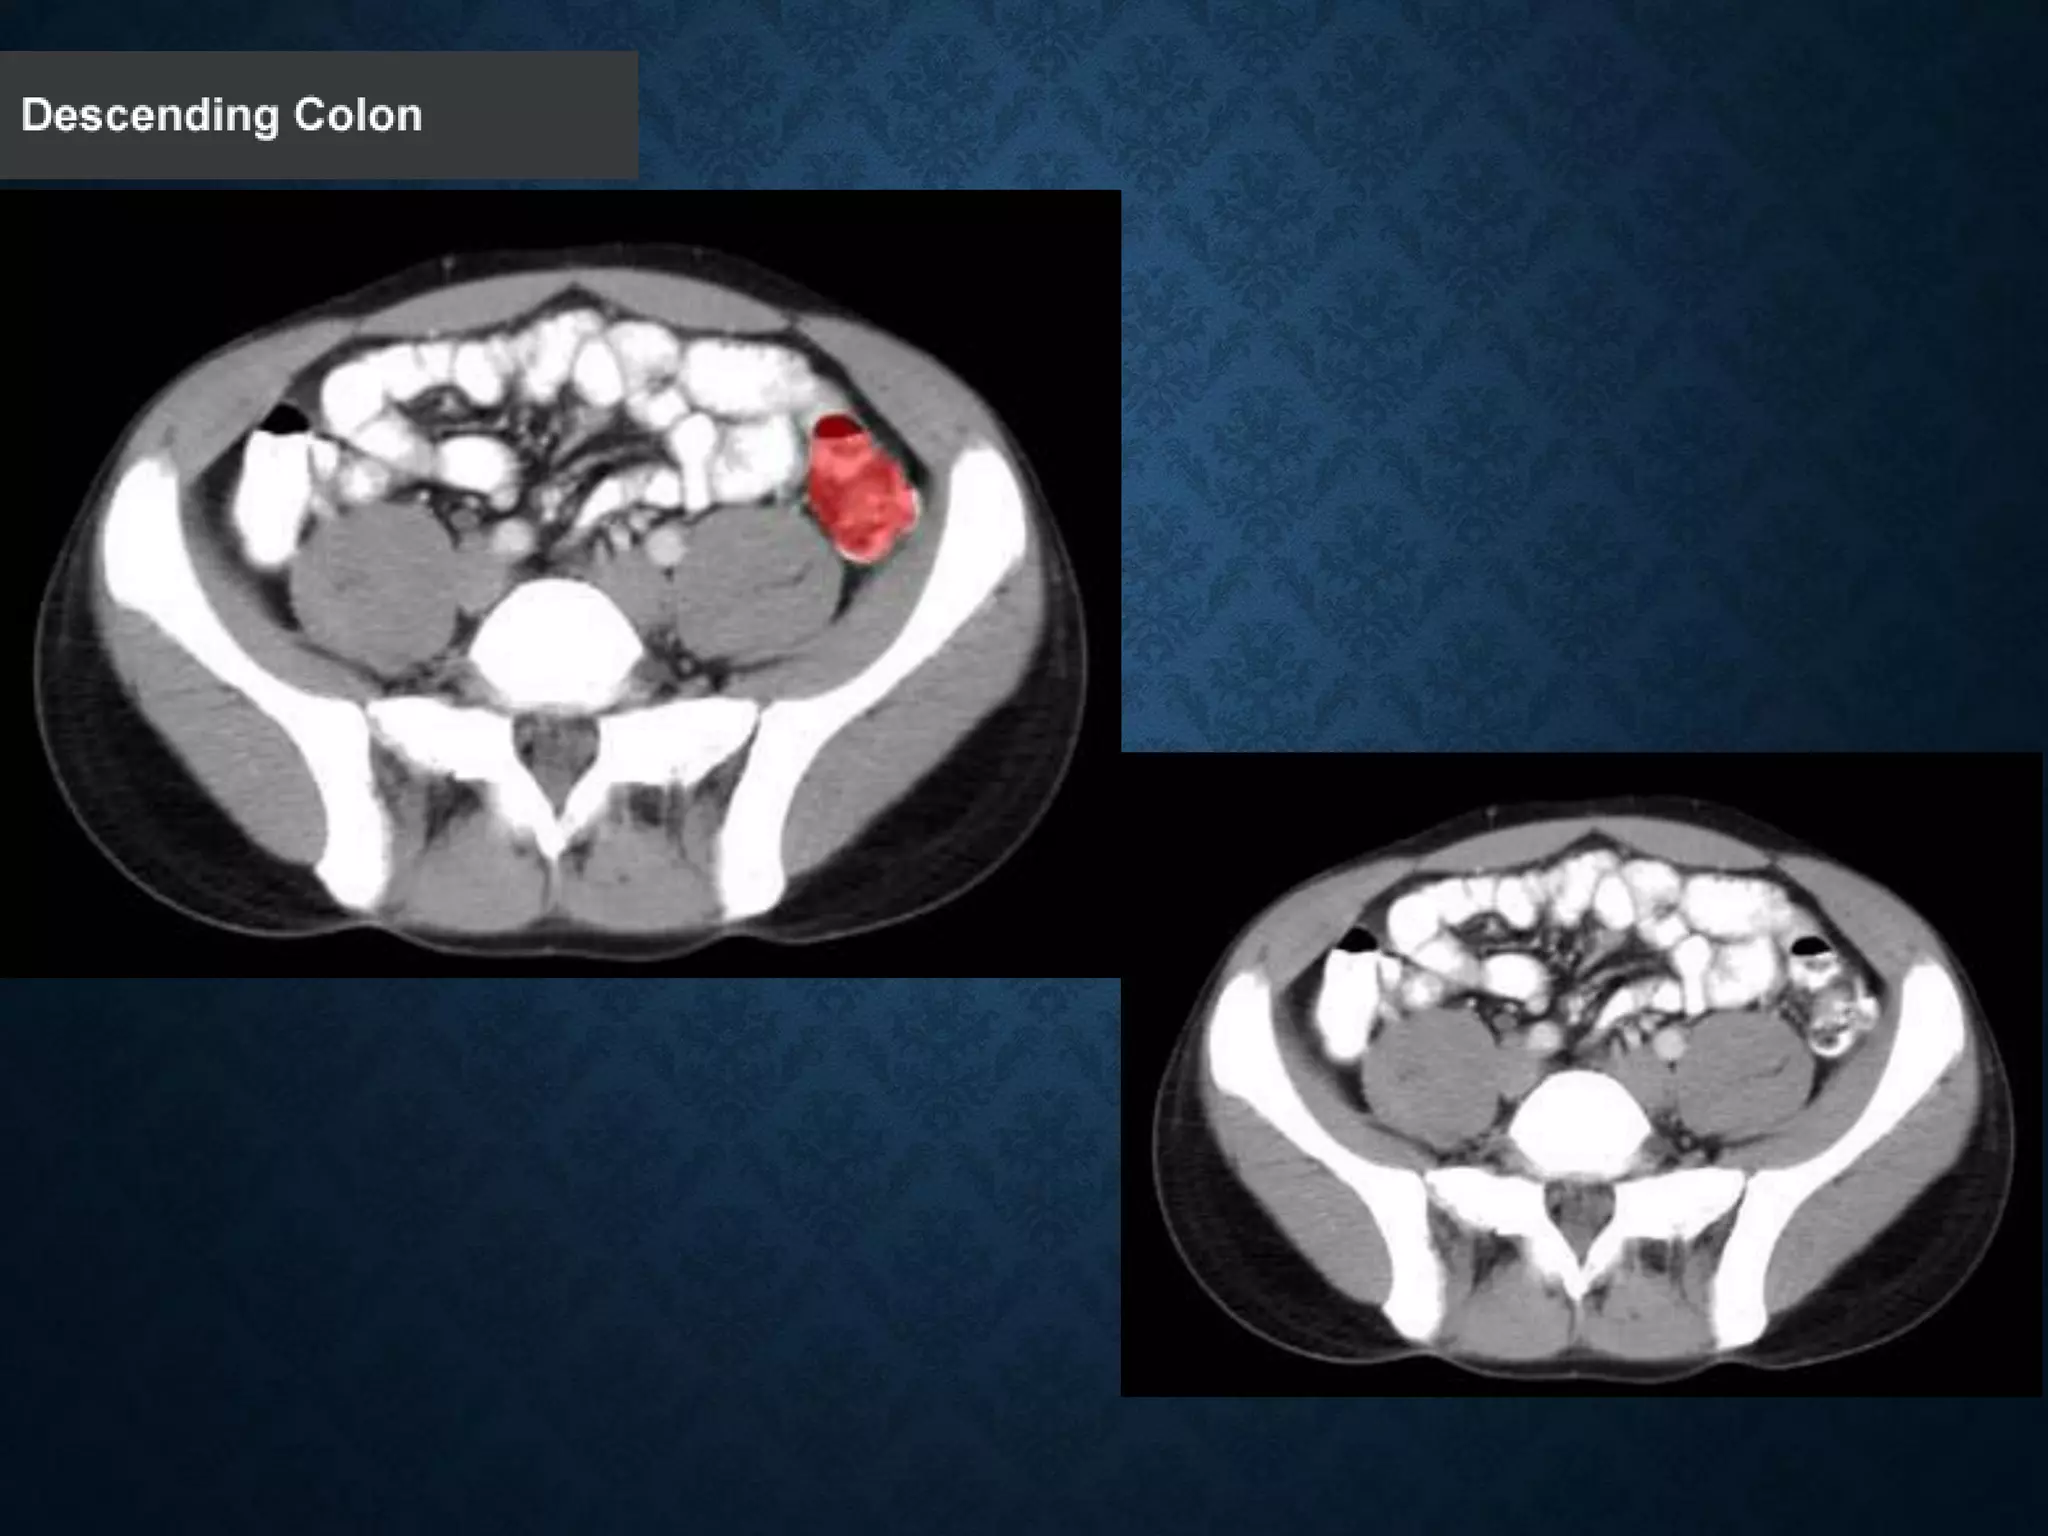

Normal Anatomy- Section 12

Normal Anatomy- Section 13